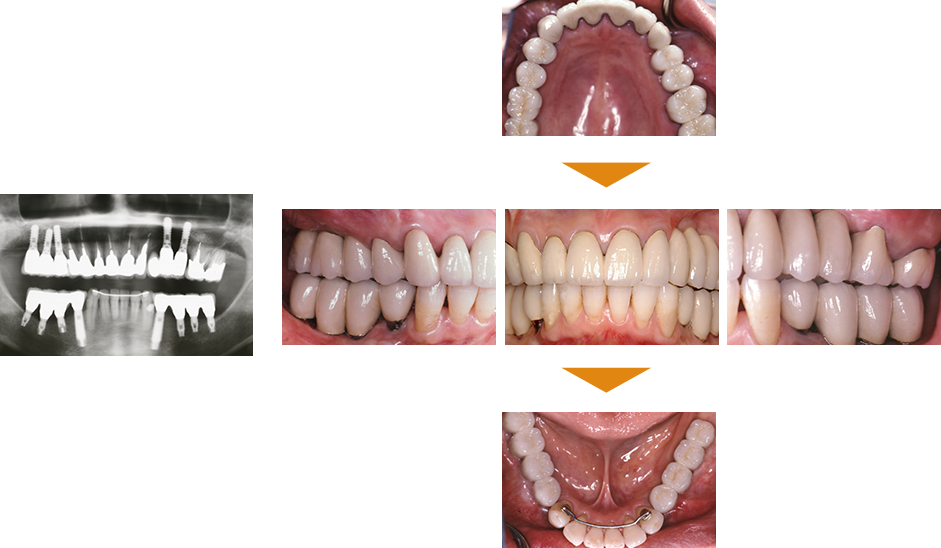

症例2

単独歯 インプラント即時荷重

|

| 治療期間 | 約4カ月 |

|---|

| 費用 | インプラント治療費 400,000円

造骨費用 50,000円

合計 450,000円(税込) |

|---|

※状態により、骨補填等別途で費用が発生する場合もございます。